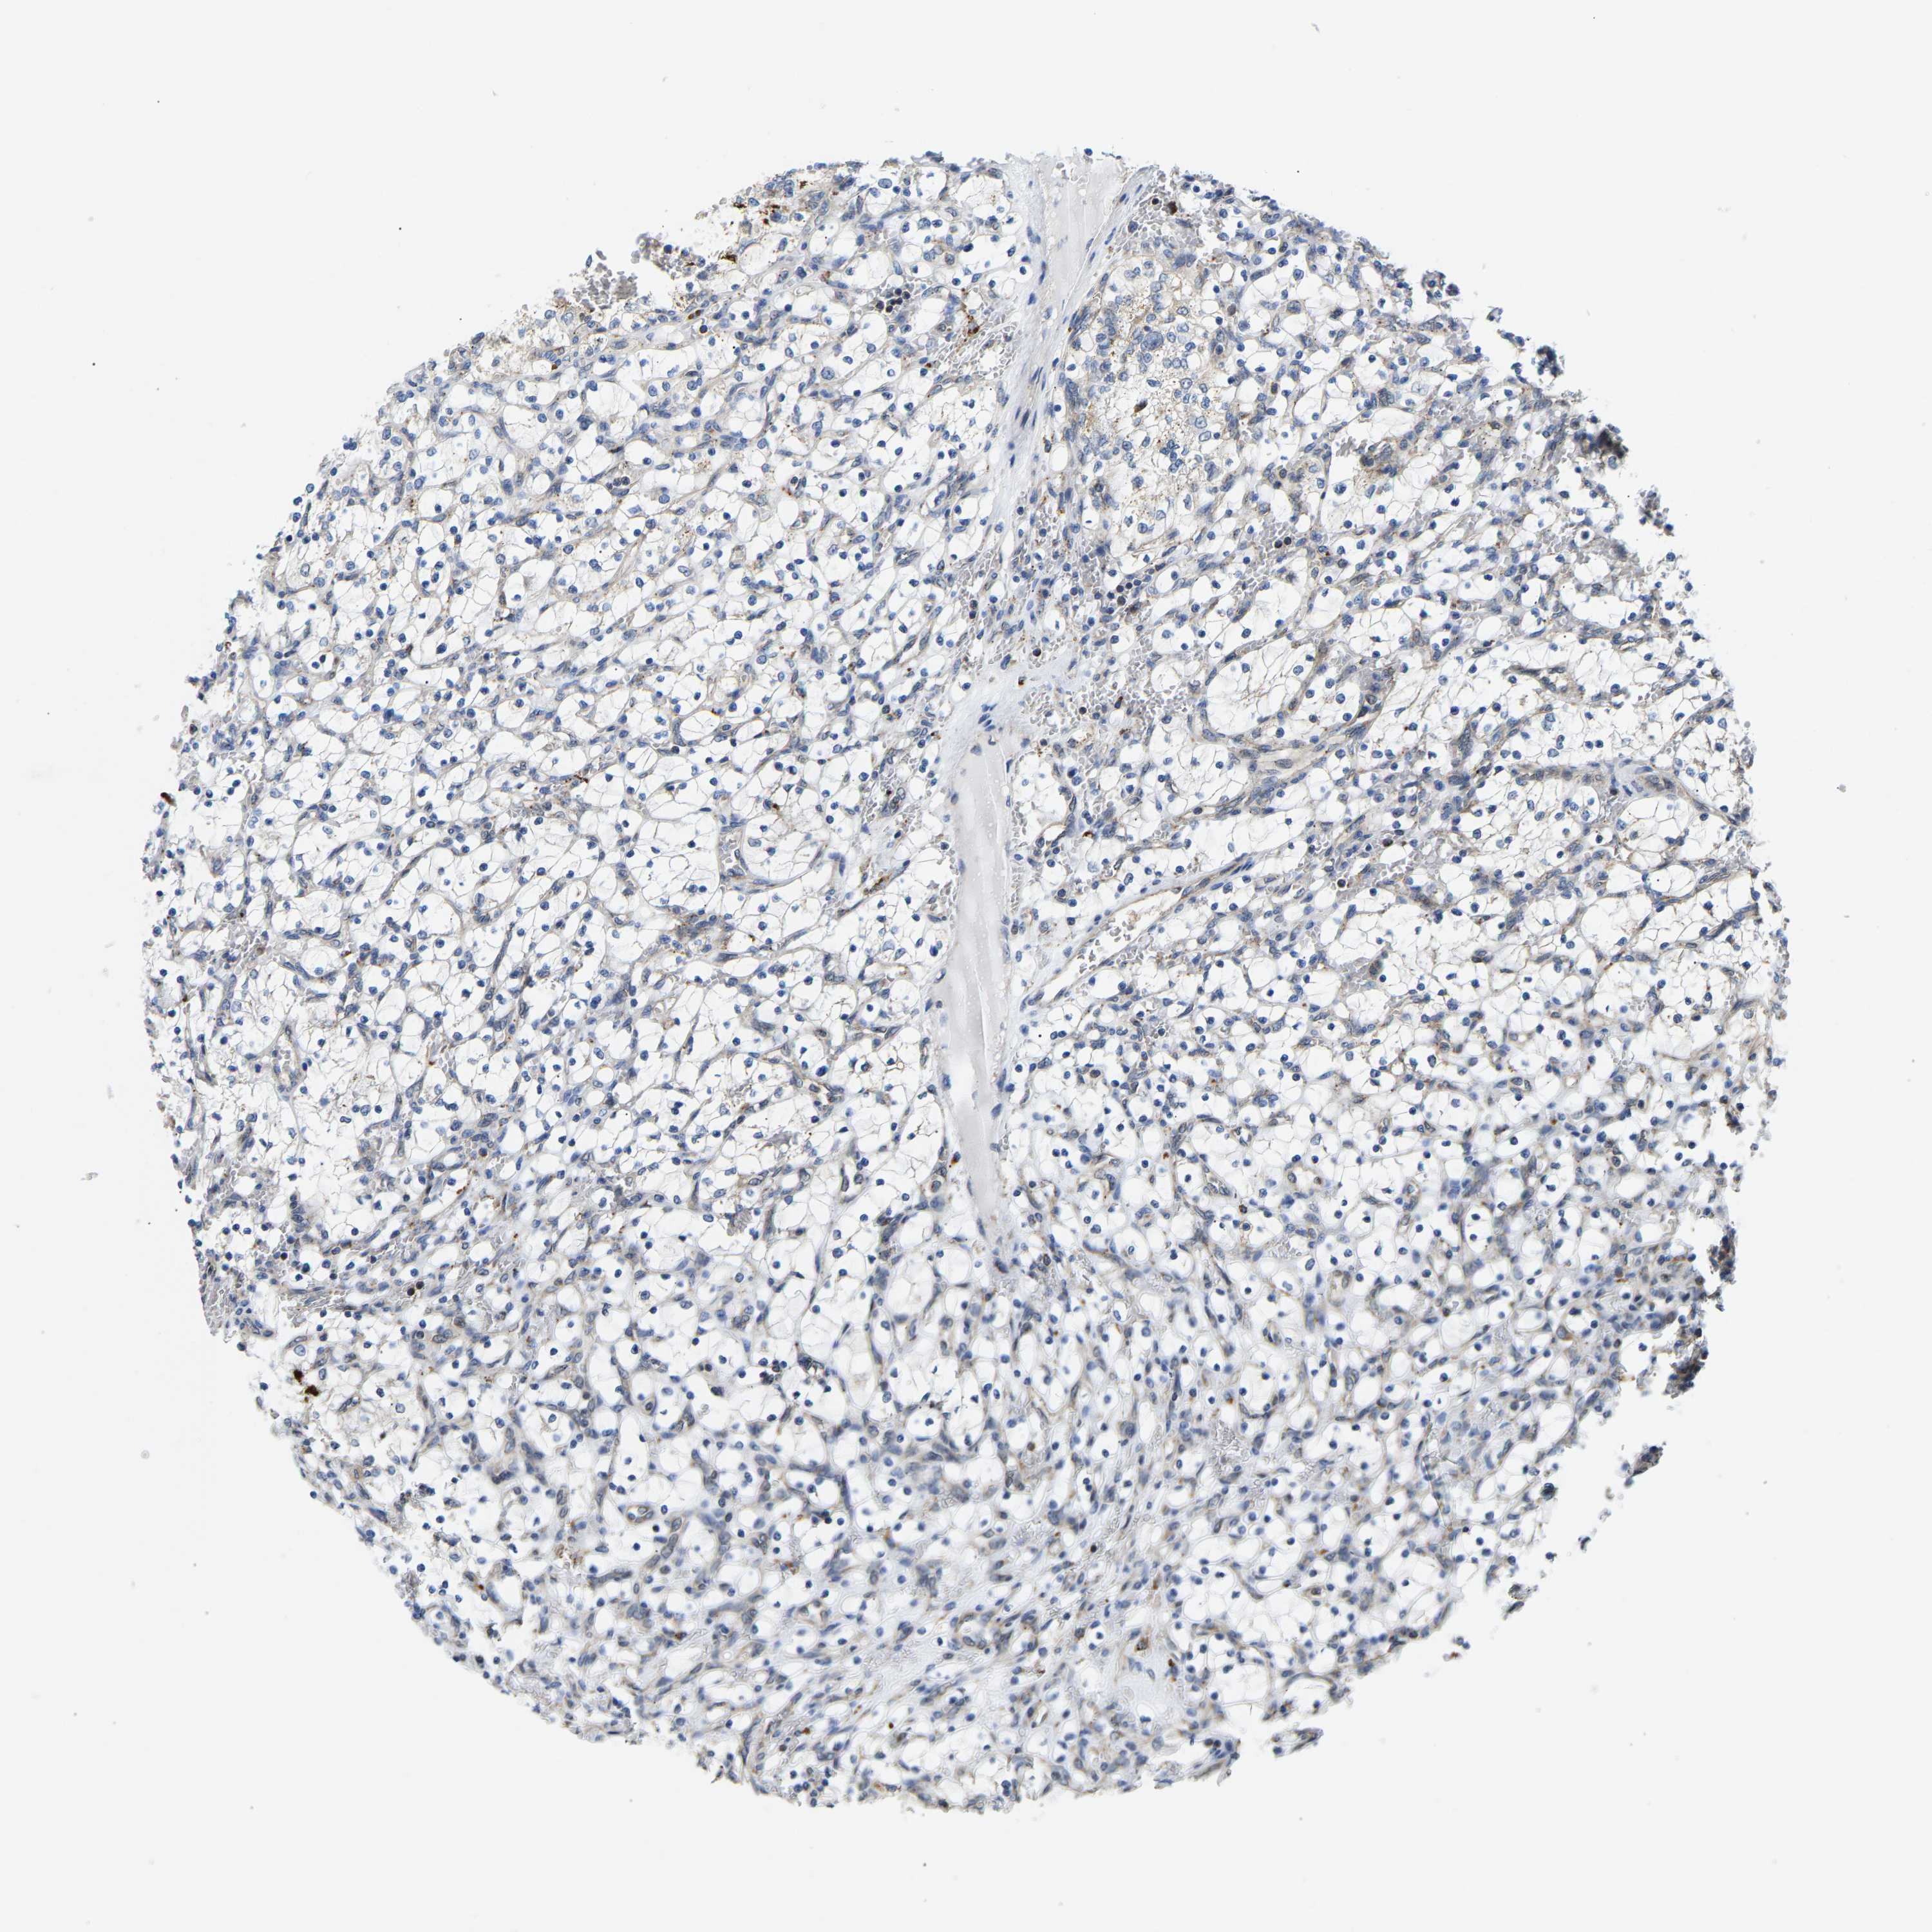

KIDNEY RENAL CLEAR CELL CARCINOMA (VALIDATION) - Interactive survival scatter ploti

The Survival Scatter plot shows the clinical status (i.e. dead or alive) for all individuals in the patient cohort, based on the same data that underlies the corresponding Kaplan-Meier plots. Patients that are alive at last time for follow-up are shown in blue and patients who have died during the study are shown in red.

The x-axis shows the expression levels (FPKM) of the investigated gene in the tumor tissue at the time of diagnosis. The y-axis shows the follow-up time after diagnosis (years). Both axes are complimented with kernel density curves demonstrating the data density over the axes. The top density plot shows the expression levels (FPKM) distribution among dead (red) and alive patients (blue). The right density plot shows the data density of the survived years of dead patients with high and low expression levels respectively, stratified using the cutoff indicated by the vertical dashed line through the Survival Scatter plot. This cutoff is automatically defined based on the FPKM cutoff that minimizes the p-score. The cutoff can be changed by dragging the vertical line or by entering a cutoff value in the square labeled "Current cut-off".

Under the Survival Scatter plot the p-score landscape (black curve; left axis) is shown together with dead median separation (red curve; right axis). Dead median separation is the difference in median mRNA expression between patients who have died with high and low expression, respectively. It is calculated as follows: median FPKM expression of dead patients with high expression - median FPKM expression of dead patients with low expression. This is intended to aid the user in visually exploring custom cutoffs and the associated p-scores and dead median separation.

Individual patient data is displayed and can be filtered by clicking on one or more of the category buttons on the top of the page. Categories describing expression level and patient information include: high, low, alive, dead, female, male and tumor stages. The scale of the x-axis can be toggled between linear and log-scale by clicking on the "x log" button. Mouse-over function shows TCGA ID, patient information and mRNA expression (FPKM) for each patient.

& Survival analysisi

Kaplan-Meier plots summarize results from analysis of correlation between mRNA expression level and patient survival. Patients were divided based on level of expression into one of the two groups "low" (under cut off) or "high" (over cut off). X-axis shows time for survival (years) and y-axis shows the probability of survival, where 1.0 corresponds to 100 percent.

GIMAP7 is not prognostic in Kidney Renal Clear Cell Carcinoma (validation)

Best expression cut offi

Based on the FPKM value of each gene, patients were classified into two groups and association between prognosis (survival) and gene expression (FPKM) was examined. The best expression cut-off refers the FPKM value that yields maximal difference with regard to survival between the two groups at the lowest log-rank P-value. Best expression cut-off was selected based on survival analysis .

When clicking on this number, the vertical dashed line indicating cut-off, the interactive survival plot, and the Kaplan-Meier curve will be adjusted to show results based on the best expression cut-off.

: 86.01

Median expressioni

Median expression refers to the median FPKM value calculated based on the gene expression (FPKM) data from all patients in this dataset. When clicking on this number, the vertical dashed line indicating cut-off, the interactive survival plot, and the Kaplan-Meier curve will be adjusted to show results based on the median expression.

: N/A

Median follow up timei

Median follow up time refers to the median time (years) after diagnosis with this type of cancer, based on clinical data from all patients in this dataset.

P scorei

Log-rank P value for Kaplan-Meier plot showing results from analysis of correlation between mRNA expression level and patient survival.

N/A

5-year survival highi

5-year survival for patients with higher expression than the expression cutoff.

For melanoma and glioma, 3-year survival is shown.

5-year survival lowi

5-year survival for patients with lower expression than the expression cutoff.

TCGA RNA samplesi

RNA-seq data is reported as average FPKM (number Fragments Per Kilobase of exon per Million reads), generated by the The Cancer Genome Atlas (TCGA) .

Normal distribution across the dataset is visualized with box plots, shown as median and 25th and 75th percentiles. Points are displayed as outliers if they are above or below 1.5 times the interquartile range. FPKM values of the individual samples are presented next to the box plot.

Average pTPM 66.8

Number of samples 100